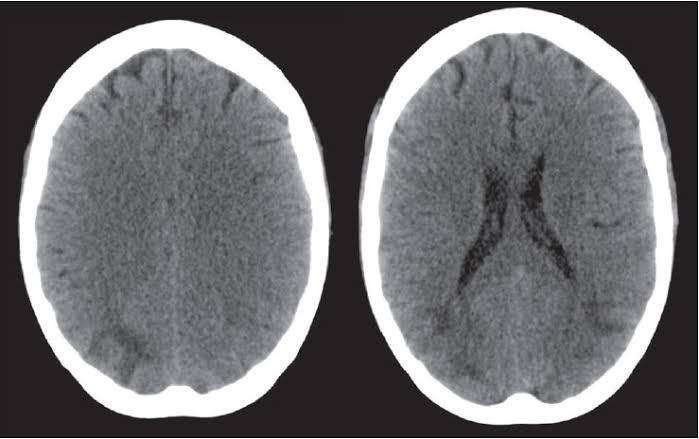

It is a very rare disease of central nervous system which affects the brain and spinal cord at the same time. When the recurrent bleeding happens into the subarachnoid space then it leads to the accumulation of hemosiderin deposits in the subpial layers of the brain and spinal cord.These hemosiderin deposits are basically the accumulations of the iron resulting from this blood. In some cases this disease is referred as superficial hemosiderosis in which the iron deposits from the blood seepage leads to the deposits in the neural tissues and this has association with the cerebrospinal fluid.

As this disease is very rare with a less understanding of the condition but the developments in MRI technique has made a lot of things clear and more understandable. The reasons behind the unintended bleeding are still unclear to some extent but the consequences can be stated clearly. When the blood accumulate in the arachnoid spaces and stays there for a longer time because of the lack of detection, then this prolonged contact of hemoglobin iron stimulates the brain’s microglial cell’s ability to biosynthesize “ferritin”. This ferritin production is considered to be harmless to brain until this excessive deposit shatter and cause damage to the neural tissues. The detailed progression behind this damage is the subsequent free radicals and lipid peroxidation caused by the over production of the ferritin by the microglial cells leading to the ultimate neural damage.